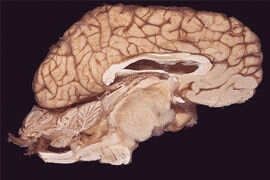

脑干(brain stem)属于脑的一部分,即脊髓向颅腔内延伸的部分。脑干位于颅后窝,自枕骨大孔至蝶鞍之间。 其下端在枕骨大孔处与脊髓相连,上端与间脑相接被大脑两半球所覆盖,它的背侧与小脑相连。脑干自下而上又可分为延髓、脑桥、中脑三段。

脑干剖面图延髓的外形:枕骨大孔至延髓脑桥沟之间。有锥体、锥体交叉、橄榄、舌下神经根、舌咽神经、迷走神经、副神经。

脑桥的外形:有脑桥基底部、脑桥基底沟、桥臂、三叉神经根、展神经、面神经、前庭蜗神经、脑桥小脑角。

中脑的外形:以视束与间脑分界,有大脑脚、脚间窝、动眼神经。